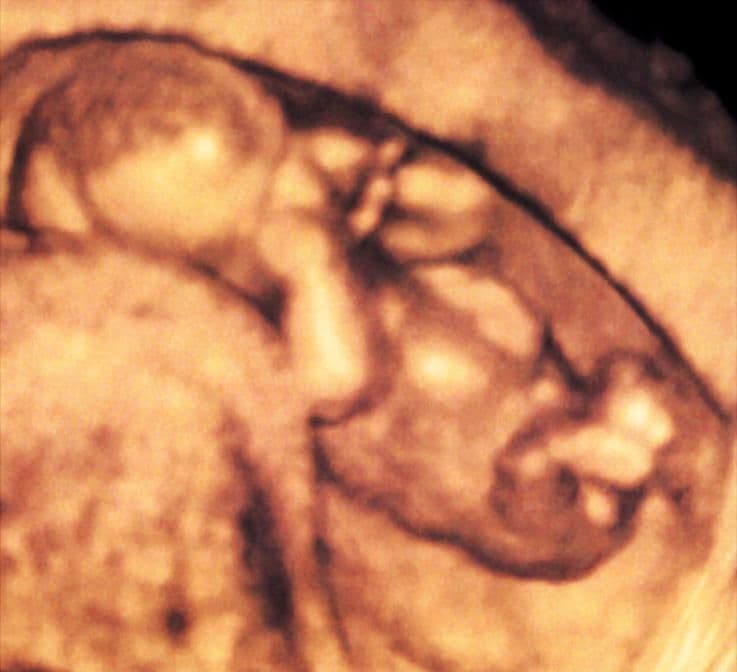

3D ultrasound scanning uses computer technology to produce more detailed images than conventional 2D scans. This scan shows a 15-week-old fetus in the uterus. At this stage all of the organs are formed, as are the vocal cords.